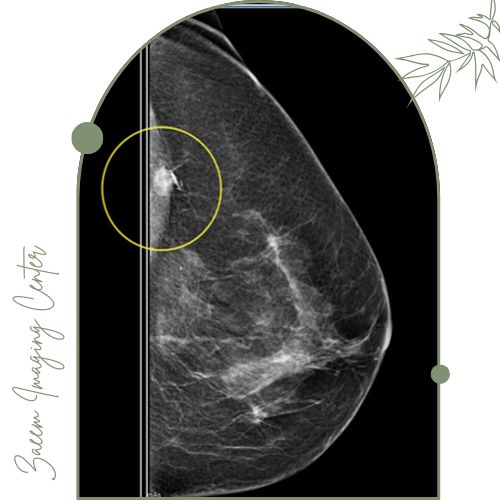

با هدایت ماموگرافی: برای ضایعاتی مانند کلسیفیکاسیون‌ها یا توده‌های کوچک که فقط در ماموگرافی دیده می‌شوند از هدایت Mammography استفاده می‌گردد.

تثبیت وایر و تصویربرداری مجدد: پس از قرارگیری سیم یک عکس سونوگرافی یا ماموگرافی گرفته می‌شود تا موقعیت وایر تأیید شود و انتهای سیم بیرون پستان ثابت گردد.